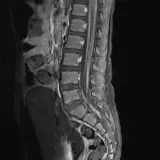

Over 2,100 interactive radiology cases, curated by radiologists for your level of training. Scroll, window, and view cases full screen โ€” just like on PACS. Click linked findings in each writeup to jump straight to them on the image. Cases include sample reports, a focused discussion section, original illustrations, and videos.

Casi completamente interattivi con gli strumenti che ti aspetti su un PACS: scroll, windowing, zoom, pan, misurazioni, ROI e modalitร  a schermo intero.

Annotazioni dettagliate evidenziano i reperti chiave direttamente sui casi. Clicca sui reperti collegati nella descrizione del caso per saltare alla loro esatta posizione sullo scan.